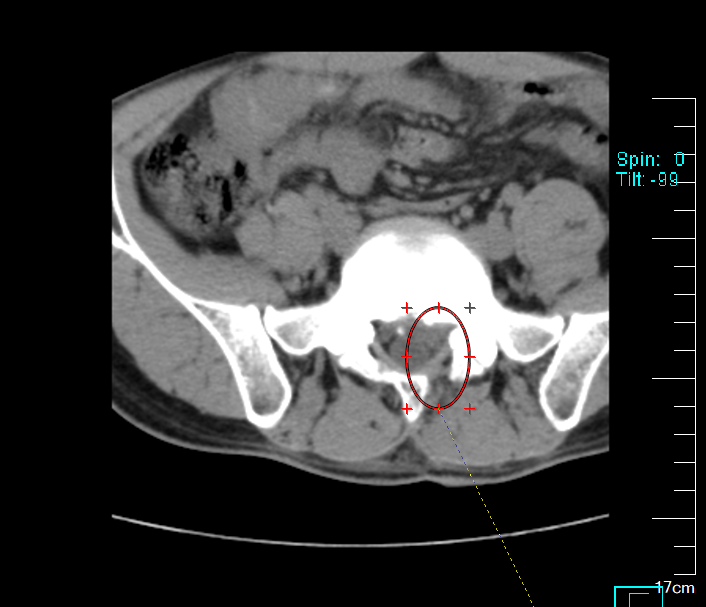

术后

整场手术历时仅100分钟,出血量约10毫升,患者全程保持清醒,术后当即感觉腿部麻木、疼痛感明显缓解。该术式为我院成熟开展的后路经椎板间入路腰椎间盘髓核摘除术(PEID),也被形象地称为“锁孔手术”,相较于传统手术,具有创伤小、恢复快、住院时间短等显著优势,特别适用于年轻、急性发作的腰椎间盘突出症患者。